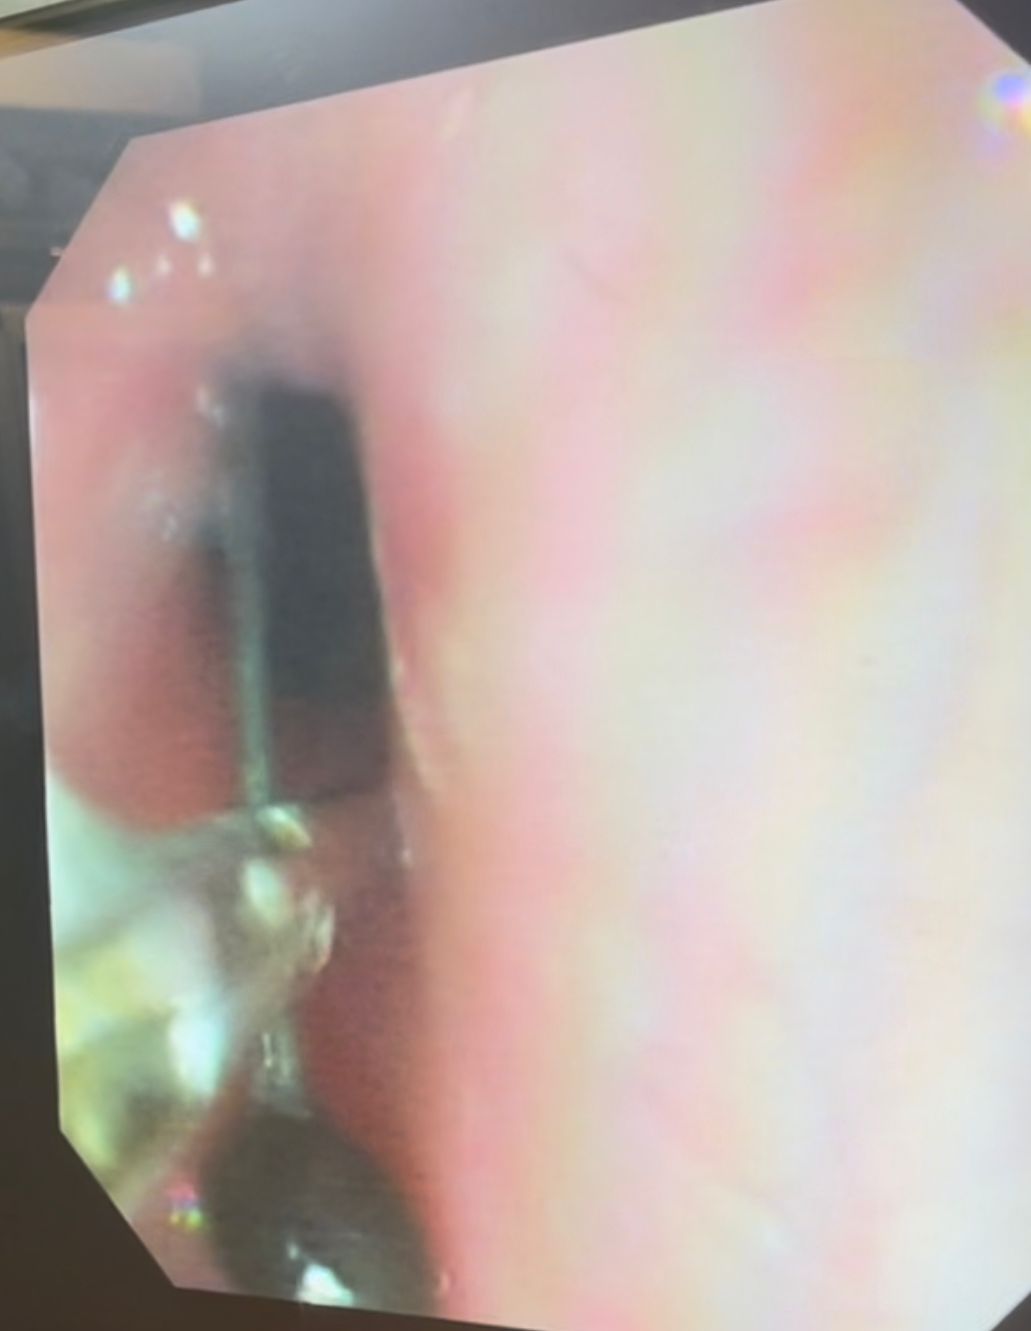

نجح فريق طبي من وحدة أمراض الجهاز الهضمي والكبد ومناظير الأطفال بقسم طب الأطفال بمستشفى سوهاج الجامعي في إجراء تدخل دقيق لاستخراج دبوس من معدة طفل يبلغ من العمر أربع سنوات، باستخدام منظار معدة خاص بالأطفال، دون حدوث أي مضاعفات، وقد غادر الطفل المستشفى بعد ثلاث ساعات فقط من الإجراء، وهو في حالة صحية جيدة.

وأكد الدكتور أحمد كمال، المدير التنفيذي للمستشفيات الجامعية، أن التعامل مع الحالة تم بسرعة وكفاءة، حيث تمكن الفريق الطبي من استخدام المنظار الخاص بالأطفال لاستخراج الدبوس دون أي تدخل جراحي، مما ساهم في خروج الطفل من المستشفى في نفس اليوم بحالة ممتازة.